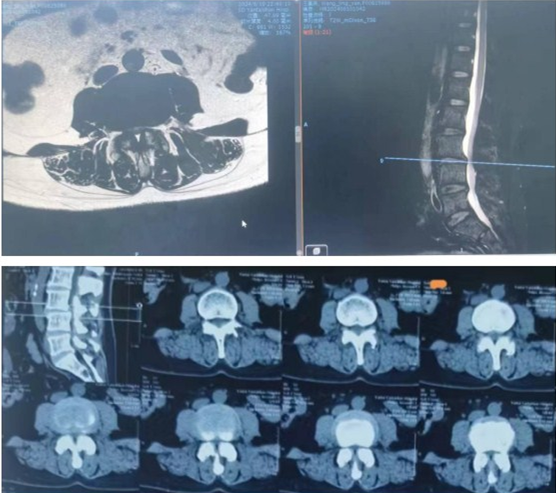

术前MRI和CT显示,患者的腰3/4椎管狭窄严重。

术后MRI显示,腰3/4椎管容积恢复神经充分。